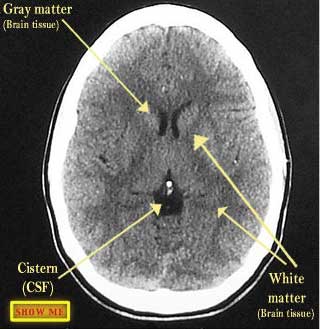

See if you can identify the structures on the right side of the patient's brain.

click to view answer